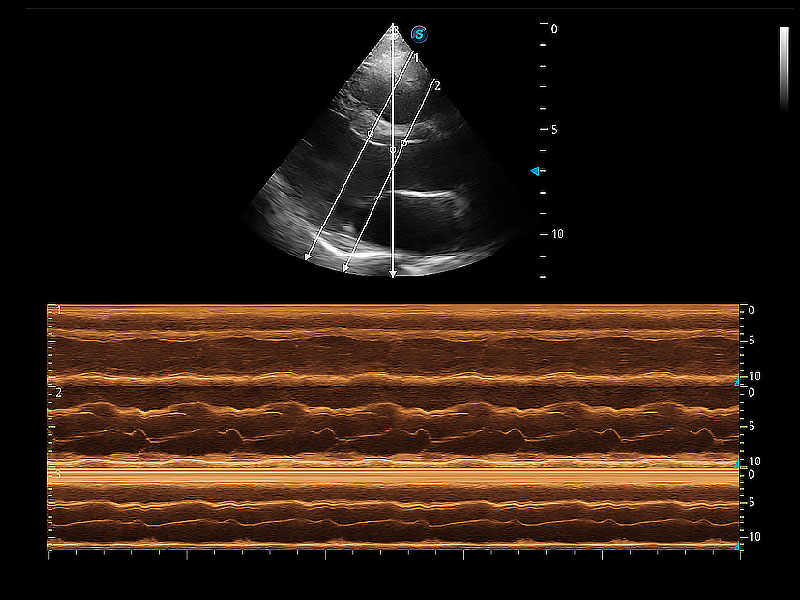

通過(guò)360度任意調(diào)節(jié)3條M型取樣線,在同一心動(dòng)周期上觀察心臟不同位置的運(yùn)動(dòng)曲線,得到準(zhǔn)確的心功能測(cè)量數(shù)據(jù),有效評(píng)估心肌運(yùn)動(dòng)及左心室功能。